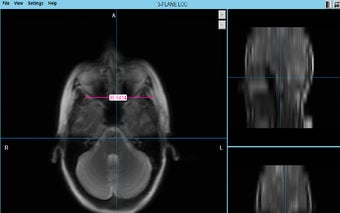

للمهنيين الطبيين والباحثين والطلاب لاستخدام تنسيق NIFTI و GIFTI و DICOM لعرض صورهم وتحليلها ومشاركتها لأغراض البحث وعرض صور DICOM و NIFTI لأنها توفر ميزات لعرض معلومات الصورة .

يوفر MRI Scalar ميزات مثل عارض الأطلس لمساعدة المستخدم في تحليل بيانات الصورة. يمكن للباحث والعالم الطبي استخدامه لإظهار هيكل المريض وتغييره لإجراء بحث طويل الأمد وتحديد موقع الورم أو الأمراض الأخرى. بالنسبة لطلاب الطب والباحثين ، فإنه يوفر القدرة على إنشاء نموذج ثلاثي الأبعاد لبيانات الصورة. p>